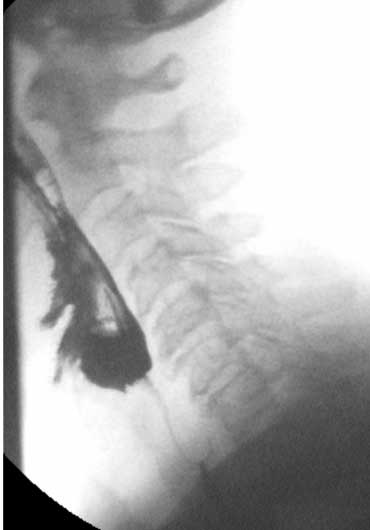

TRÁI: túi thừa nhỏ. GIỮA và PHẢI: túi thừa Zenker thực sự do đóng sớm của cơ nhẫn hầu (mũi tên vàng)

Túi thừa Zenker

Túi thừa Zenker luôn là hậu quả của rối loạn chức năng cơ nhẫn hầu.

Đóng sớm của cơ nhẫn hầu dẫn đến tăng áp lực trong hạ hầu, ngay phía trên cơ nhẫn hầu, khi sóng áp lực của các cơ khít hầu đẩy bolus xuống dưới.

Áp lực tăng này có thể gây phồng ra tại điểm yếu trên thành hầu sau (khe hở Killian).

Ban đầu sẽ tạo thành một túi nhỏ, theo thời gian có thể phát triển và hình thành túi thừa Zenker thực sự (Hình).